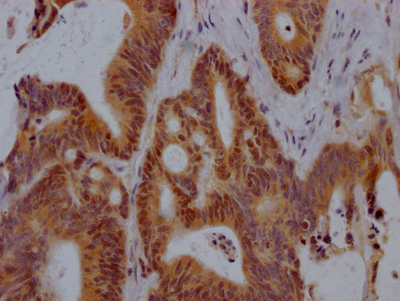

The image on the left is immunohistochemistry of paraffin-embedded Human breast cancer tissue using CSB-PA919263(SPAG4 Antibody) at dilution 1/25, on the right is treated with synthetic peptide. (Original magnification: ×200)

The image on the left is immunohistochemistry of paraffin-embedded Human thyroid cancer tissue using CSB-PA919263(SPAG4 Antibody) at dilution 1/25, on the right is treated with synthetic peptide. (Original magnification: ×200)